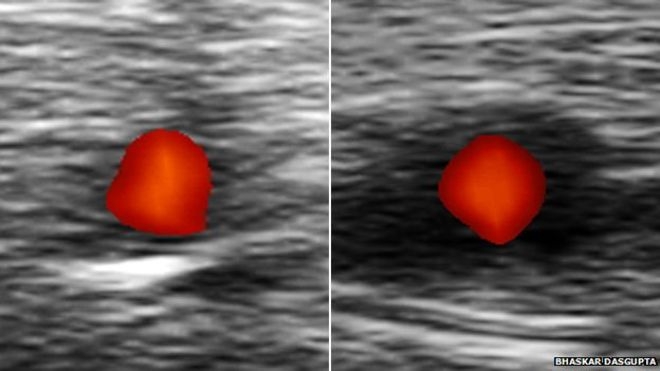

Cualquier persona que se sospeche que pueda padecer esta enfermedad debería ser analizada con ultrasonido. Si un paciente tiene ACG, el escáner mostrará una banda oscura alrededor de la arteria temporal.

Este tipo de diagnóstico, creado por un especialista reumatólogo llamado Bhaskar Dasgupta y que da resultados en muy poco tiempo, redujo el número de casos de 17 al año a sólo uno en el hospital universitario de Southend.